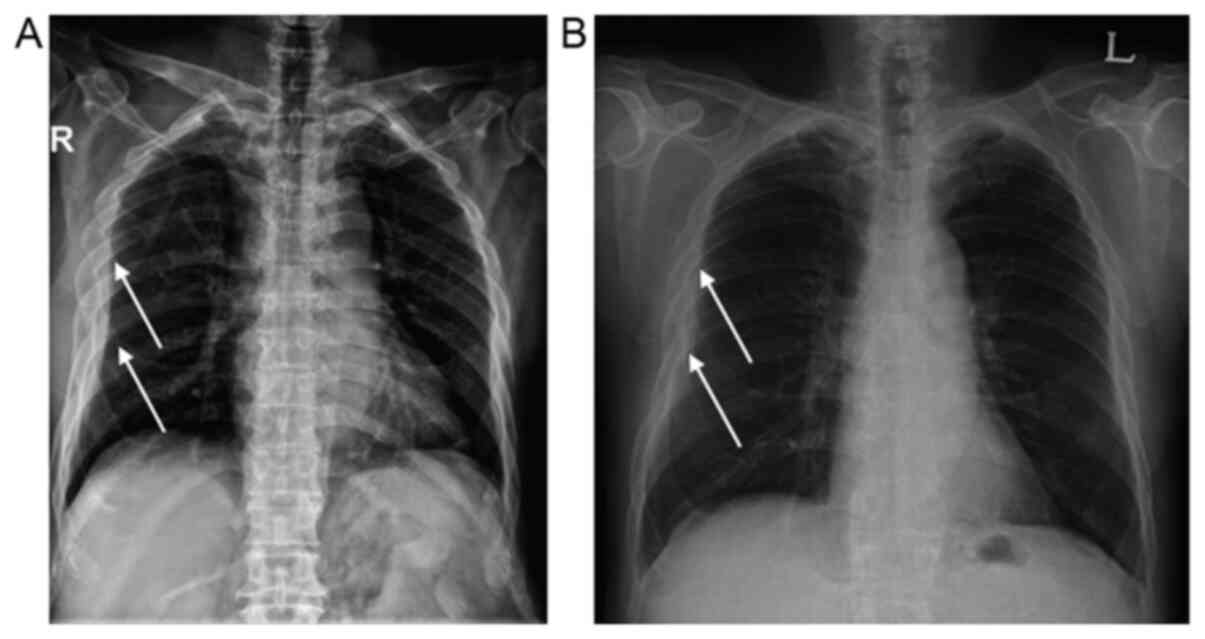

Spontaneous intermuscular hematoma in a patient receiving ticagrelor and aspirin: A case report

Dual antiplatelet therapy is a cornerstone treatment following percutaneous coronary intervention (PCI) for acute coronary syndrome (ACS). Ticagrelor, a direct‑acting potent P2Y12 inhibitor, is superior to clopidogrel in the acute setting of ACS: due to its faster onset and potent antiplatelet inhibition. Thus, ticagrelor is becoming widely recommended as the as the initial treatment following PCI in current guidelines. However, due to its potency, the risk of bleeding is higher. Herein, a report of an unusual case of spontaneous intermuscular hematoma is described. Furthermore, single‑nucleotide polymorphisms that may be related to bleeding in ticagrelor using population‑based genome‑wide association studies were also identified and are discussed. As there is a concern that patients of Asian origin may have a higher risk of bleeding, physicians must be made aware of this risk when prescribing ticagrelor to individuals of Asian decent.

Figure 1

Figure 2